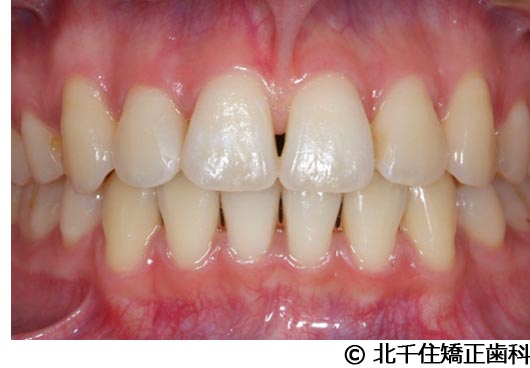

【症例3】叢生

- 治療前

- 治療後

- 治療名

- 叢生

- 費用

- 1,125,000円(税込)

- 期間

- 2年1ヵ月

- 治療回数

- 26回

- 通院頻度

- 1ヵ月ごと

- 年齢・性別

- 19歳3ヵ月・女性(初診時)

治療内容

-

患者様の症状

主訴:デコボコ、口元の突出

治療方法

上下顎第一小臼歯4本を抜歯してワイヤー矯正(セラミックブラケット)。

治療結果

叢生に対し抜歯を併用した矯正治療により、歯列および咬合関係の調整を行った症例である。治療後は保定装置を使用し、歯列および咬合の安定維持を目的として定期的な経過観察を行っている。

※治療結果は個人差があります。

治療を行う上での注意点(リスク・副作用)

歯磨き不良に伴うカリエスや歯周病、歯根吸収など。